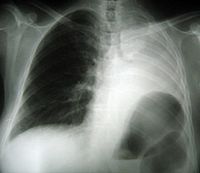

On admission, the patient had a 38°C temperature, 87 beats/min pulse, 130/70 mmHg blood pressure with a 95% oxygen saturation while breathing room air. Respiratory crackles were heard over the left lung field. The rest of the clinical examination was normal. Full blood count, serum chemistries, renal and liver function tests were normal. The screening for human immunodeficiency virus was negative. Sputum cultures were sterile for bacteria, fungi and acid fast bacilli. A bone marrow aspirate and biopsy was normal. A chest X- Ray revealed a left parahilar opacity (Figure 1). Chest CT-scan (Figure 2) revealed a bronchial tumour mass of the left superior lobe classified as T3N0MO: stage IIIA. Bronchoscopy showed an incomplete stenosis by an infiltration of the upper lobe. Biopsies revealed nonspecific inflammation. An extrapericardic left pneumonectomy was performed because of the high suspicion of lung carcinoma. The immuno-histochemical staining showed a polymorphous lymphoid infiltrate expressing CD3+ T cells and CD20+ and CD30+ B cells, and a perivascular infiltrate with extensive tissue necrosis in keeping with angiitis; these findings were consistent with the diagnosis of LYG grade 2 by WHO classification (Figure 3). The patient refused any adjuvant chemotherapy. There was no evidence of any clinical or radiological signs of relapse three years after surgery (Figure 4).

Figure 1. A chest X- Ray showing a left parahilar opacity